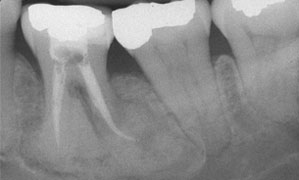

Minor radiolucency could be recognized around the roots while the high dense deposit within the bone is obvious at the mandibular associated lesions. Intraoral examination showed that the maxilla was completely edentulous; the mandible contained only six teeth: This evolution may take months or years, and during its development, the diameter of the lesion increases from 0.

Biopsy specimens were sent to the Department of Oral Pathology, where sections were cut and prepared conventionally, and stained with hematoxylin and eosin. This Article Anticancer Research May vol. Lam is associate professor and head, discipline of oral and maxillofacial radiology, faculty of dentistry, University of Toronto, Toronto, Ontario. Endoral radiography showed that these teeth had been devitalized; they had deep periodontal pockets and marked radicular radiotransparency; the root apices exhibited mixed radiotransparency and radio-opacity.

A complete or partial radiolucent dyslpasia was noted in a few reports 12,13,22 and a sclerotic border has been less frequently reported 2,14,22 Fig. None of her family reported to have similar conditions. Clinical, radiographic, and histological findings of florid cemento-osseous dysplasia: Of the patients for whom age and sex were known, the majority 97 [ In this retrospective analysis, COD more usually occurs in the mandible, both in tooth-bearing and edentulous areas, but may occasionally occur in the maxilla.